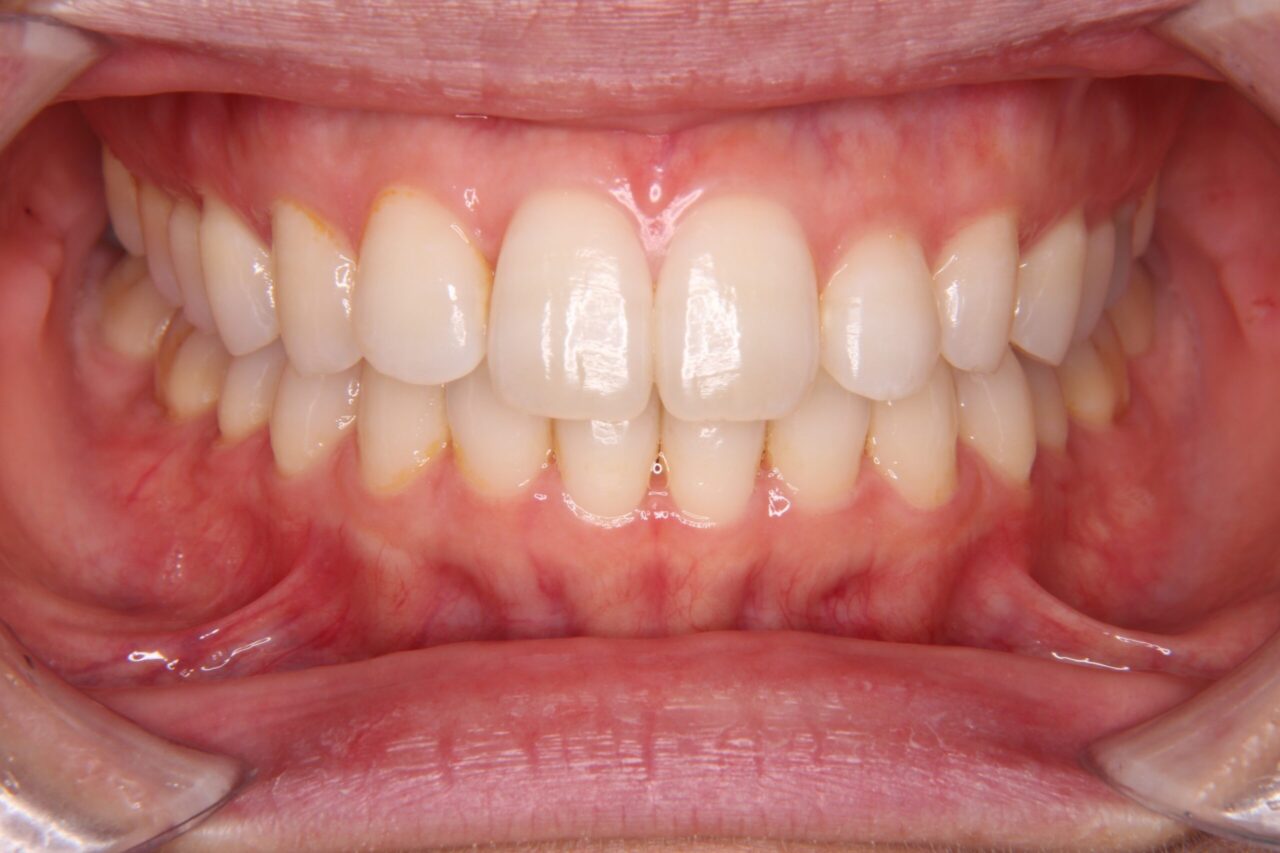

矯正後の歯列

矯正後の歯列がこちらです↓↓↓

私自身、矯正でコンプレックスだった歯並びの改善ができて、本当に良かったと思っています!